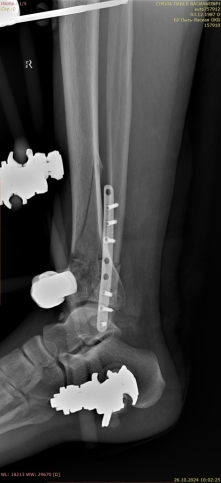

Через 6 дней, после спадения отека, был выполнен открытый накостный остеосинтез большеберцовой кости блокируемыми пластинами (рис. 3).

Рис. 3.